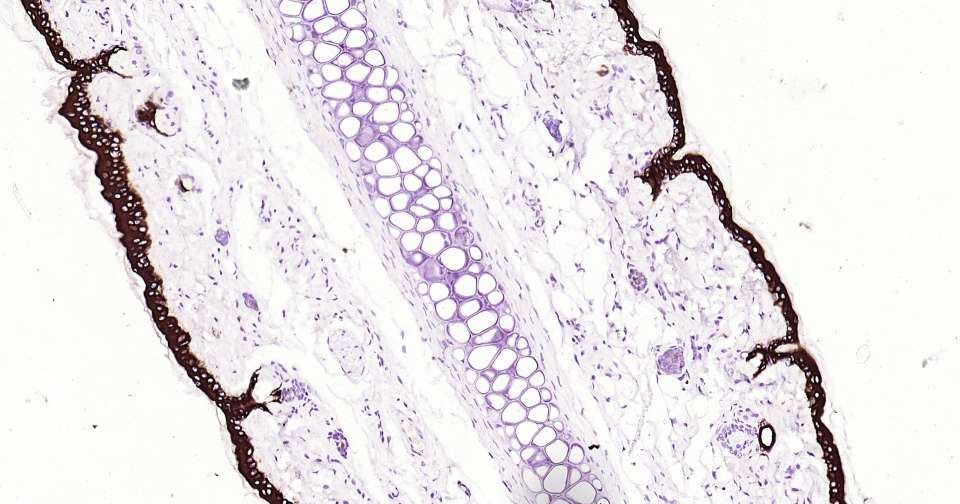

Immunohistochemical analysis of paraffin embedded mouse skin tissue slide using IHC0360 (CK10/Cytokeratin 10 Kit).

Immunohistochemical analysis of paraffin embedded human skin tissue slide using IHC0360 (CK10/Cytokeratin 10 Kit).

Immunohistochemical analysis of paraffin embedded rat skin tissue slide using IHC0360 (CK10/Cytokeratin 10 Kit).